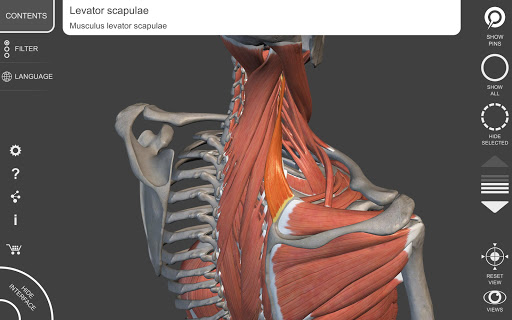

"Anatomía - Atlas 3D" permite estudiar la anatomía humana de forma fácil e interactiva.

A través de una interfaz sencilla e intuitiva es posible observar cada estructura anatómica desde cualquier ángulo.

Los modelos anatómicos 3D son especialmente detallados y con texturas de hasta una resolución de 4k.

La subdivisión por regiones y las vistas predefinidas facilitan la observación y el estudio de partes individuales o grupos de sistemas y las relaciones entre los diferentes órganos.

MODELOS ANATÓMICOS 3D

• Sistema musculoesquelético

nervioso • Sistema respiratorio • Sistema digestivo • Sistema urogenital (masculino y femenino) • Sistema endocrino • Sistema linfático • Sistema ocular y auditivo CARACTERÍSTICAS • Interfaz sencilla e intuitiva • Rotar y hacer zoom en cada modelo en el espacio 3D • Opción para ocultar o aislar uno o varios modelos seleccionados • Filtro para ocultar o mostrar cada sistema • Función de búsqueda para encontrar fácilmente cada parte anatómica • Función de marcador para guardar vistas personalizadas • Rotación inteligente que mueve el centro de rotación automáticamente • Función de transparencia • Visualización de músculos a través de niveles de capas desde las superficiales hasta las más profundas • Al seleccionar un modelo o un pin, aparece el término anatómico relacionado • Descripción de los músculos: origen, inserción, inervación y acción • Mostrar/ocultar interfaz de usuario (muy útil con pantallas pequeñas) MULTILINGÜE • Los términos anatómicos y la interfaz de usuario están disponibles en 11 idiomas: latín, inglés, francés, alemán, italiano, portugués, turco, ruso, español, Chino, japonés y coreano • Los términos anatómicos se pueden mostrar en dos idiomas simultáneamente REQUISITOS DEL SISTEMA • Android 8.0 o posterior, dispositivos con al menos 3 GB de RAM Reversi